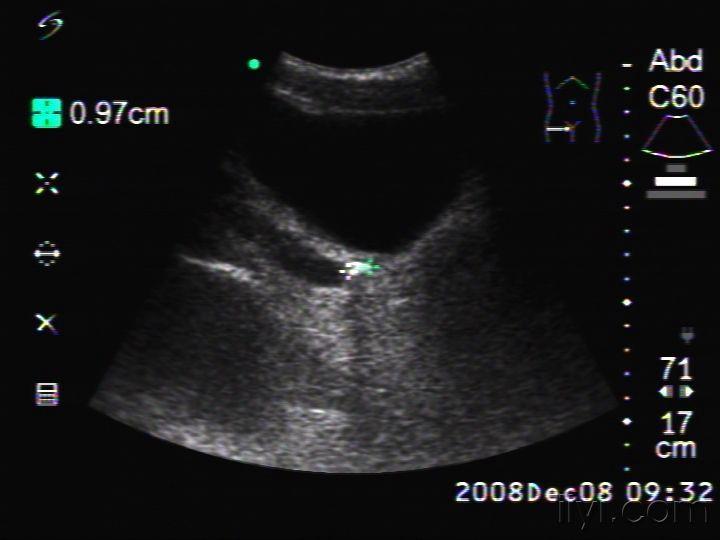

碎石前彩超示:左侧输尿管下段结石